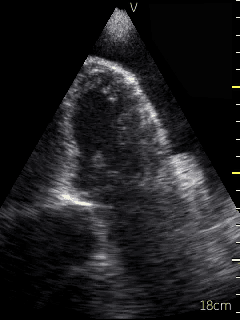

Video 1 (online supplement; Figure 1) demonstrates a parasternal long axis view with the pericardial effusion noted to be posterior to the left ventricle in this view. Video 2 (online supplement; Figure 2) is a short axis view of the heart which is showing that the effusion is surrounding the heart. Video 3 and 4 (online supplements; Figures 3 & 4) demonstrates that the pericardial effusion is present significantly surrounding the apex as well. An echocardiogram confirmed the POCUS findings and cardiology was consulted to conduct a pericardiocentesis, following which the patient’s symptoms resolved. The effusion was thought to be chronic and transudative. In this case, the use of POCUS at the bedside allowed for rapid detection of a large pericardial effusion and subsequent treatment.